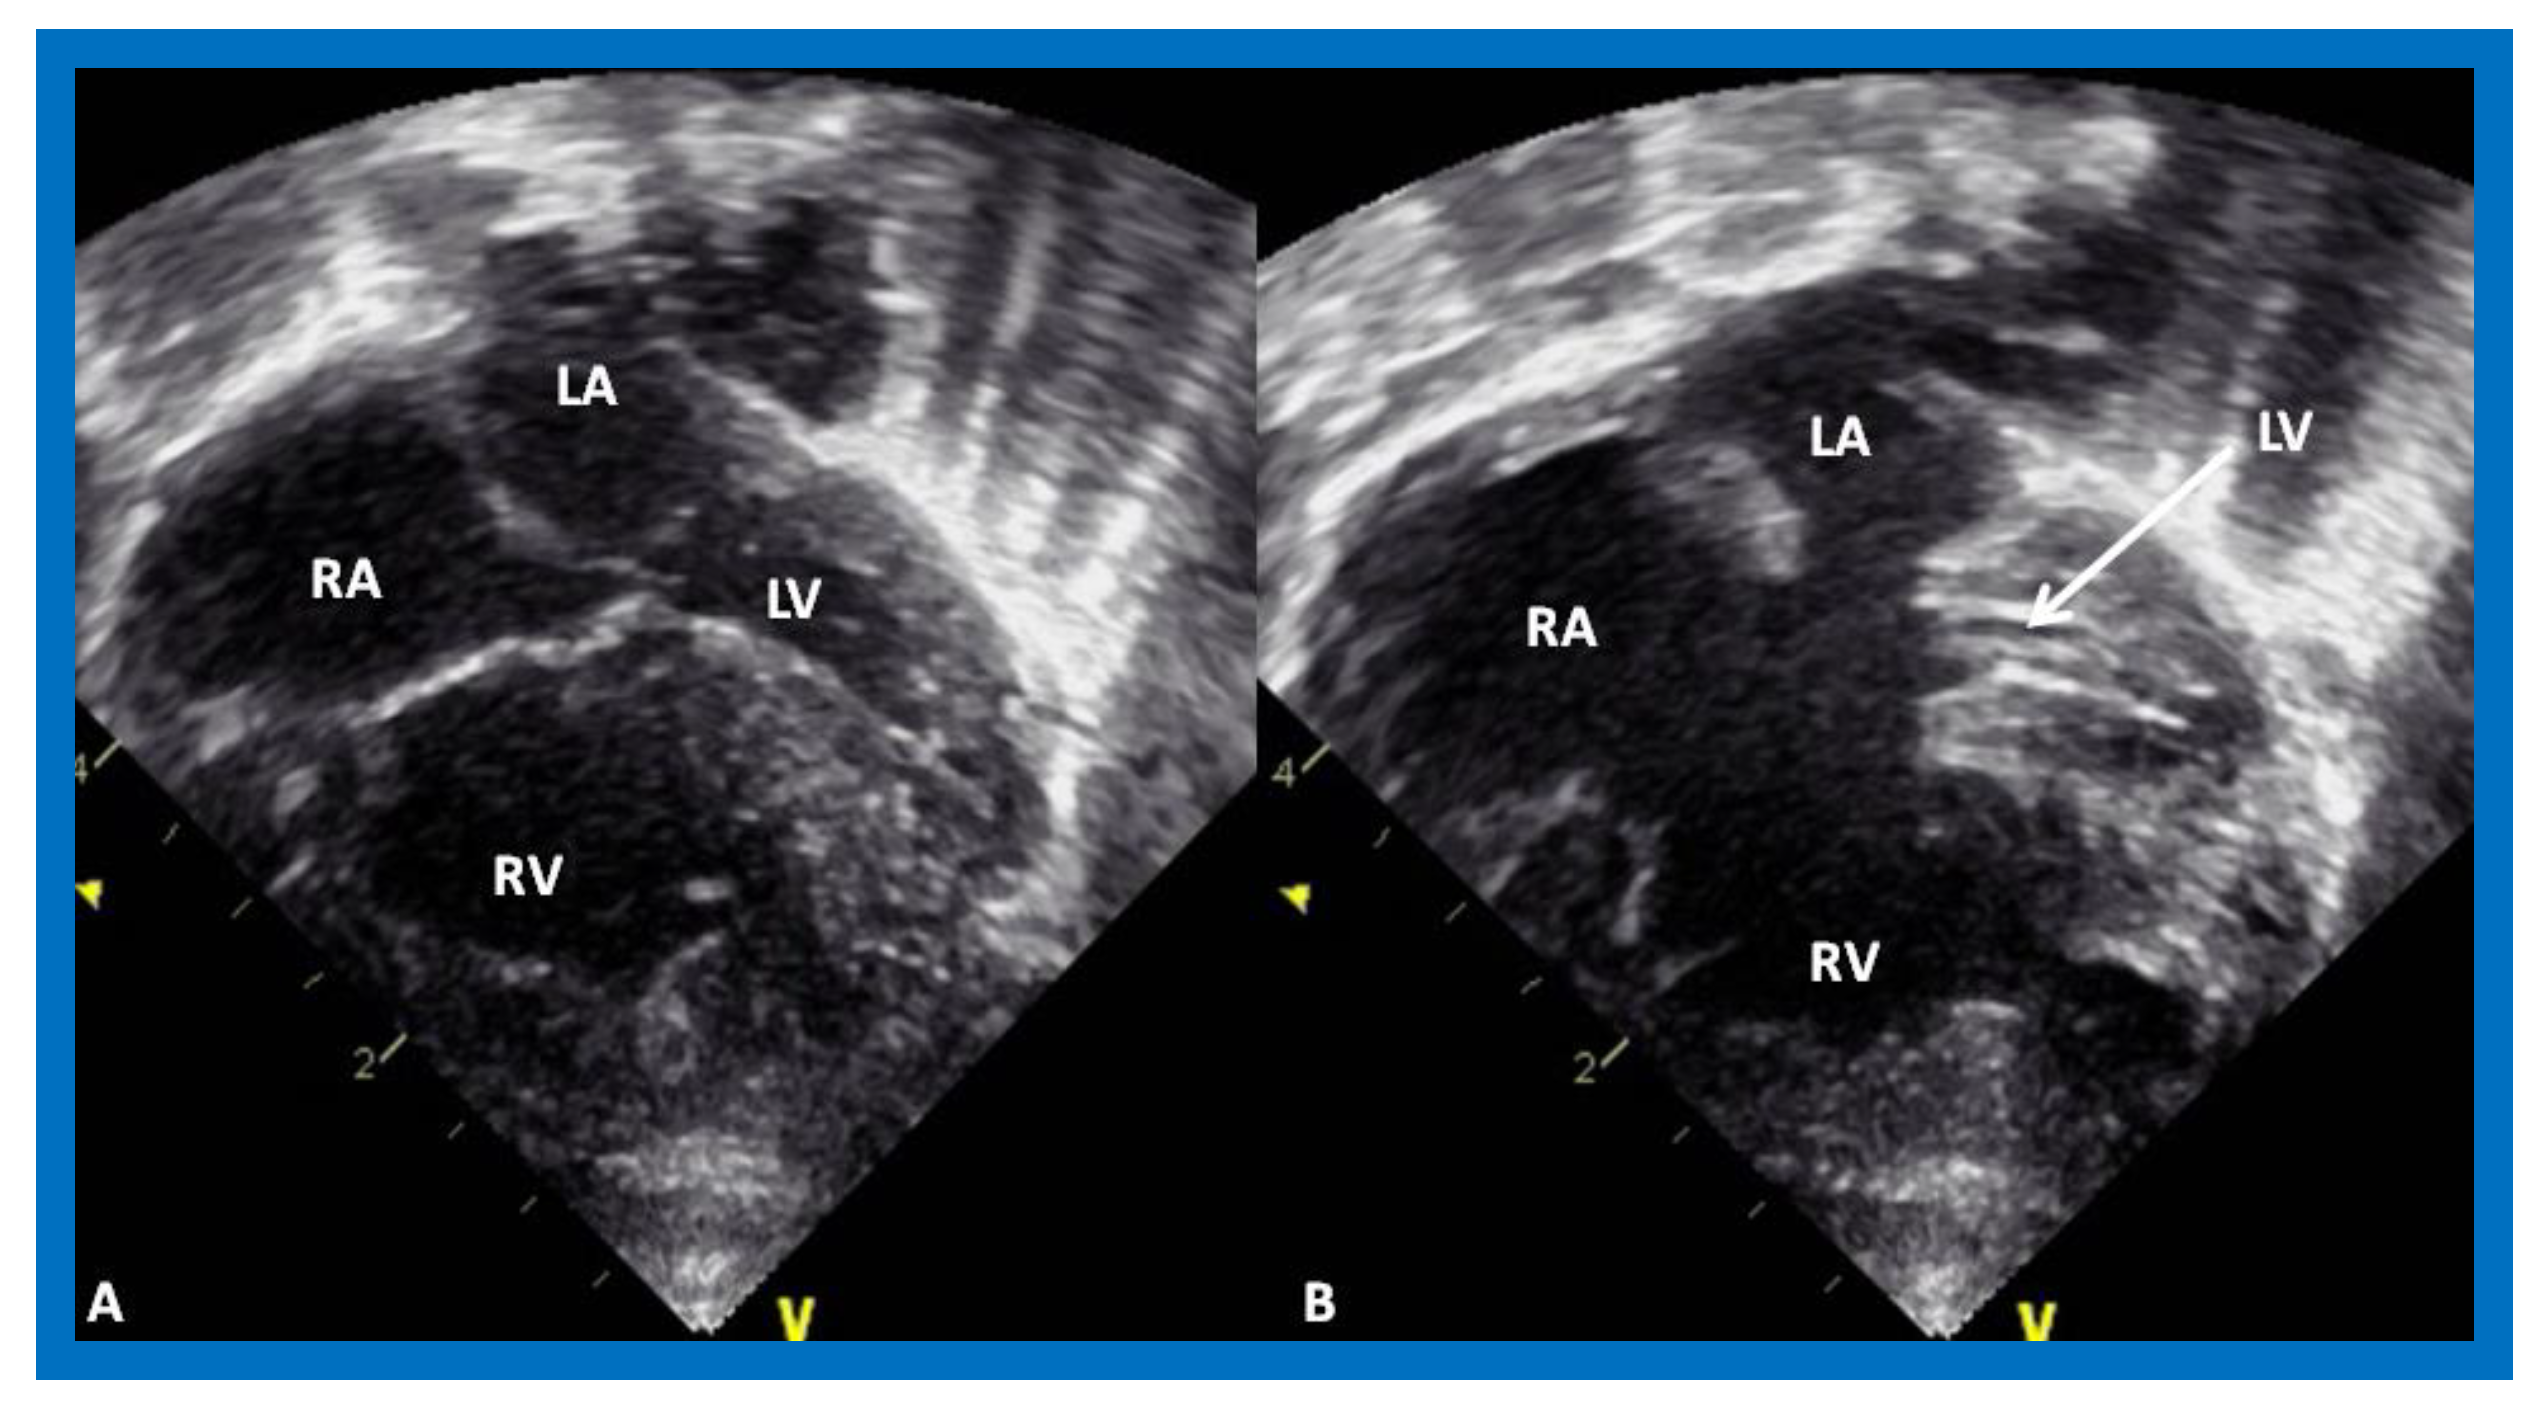

2.5. Mitral Atresia with Normal Aortic Root